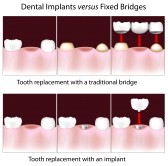

Άνω Πατήσια, Προσθετική με εμφυτεύματα, γέφυρες κεραμικές

Πατήσια, αποκαταστάσεις με εμφυτεύματα